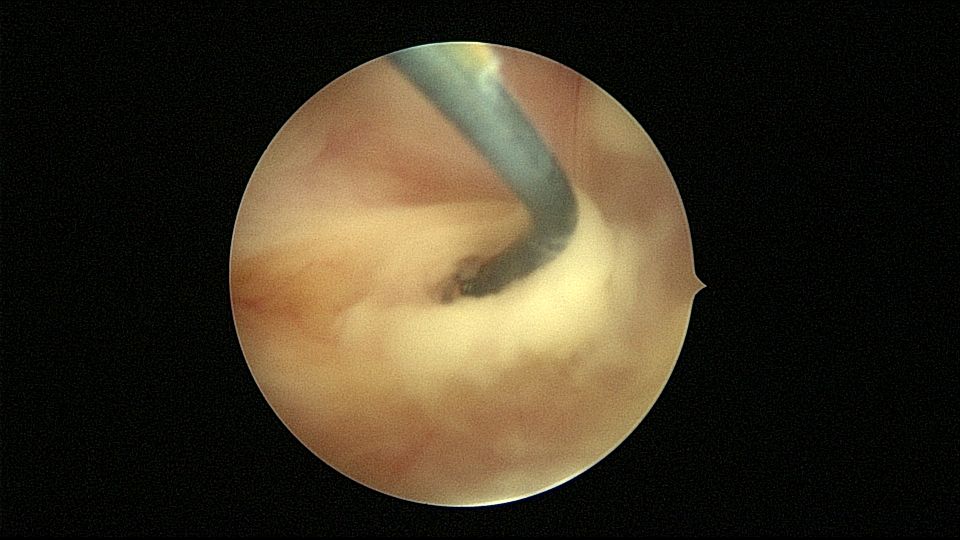

54岁,G2P1,顺产1次,安环16年,绝经10年,无不适症状,B超提示节育器嵌顿,宫腔积液2.3cm*1.9cm,血常规正常,白带常规乳酸杆菌少,其余指标正常。宫腔镜见宫颈管中上段封闭粘连,镜鞘分离粘连,见V型环一臂铜环全部嵌入右侧宫壁肌层内,取出节育器,宫腔内见灰白色脓液漂浮,膨宫液冲洗脓液,宫腔镜下无脓苔后结束手术,术后抗炎治疗。病检:宫腔少许宫内膜,呈慢性炎改变。